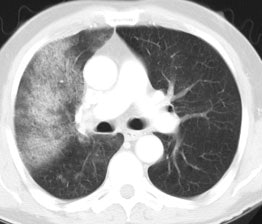

Bronchoalveolar cell carcinoma (BAC): The images below were from a patient with bronchoalveolar cell carcinoma that presented as a chronic right lung infiltrate. The FDG PET exam was positive in this case despite a higher likelihood of a false negative exams in patients with BAC. Note the most intense area of FDG accumulation corresponds to the area of greatest consolidation on CT imaging. |